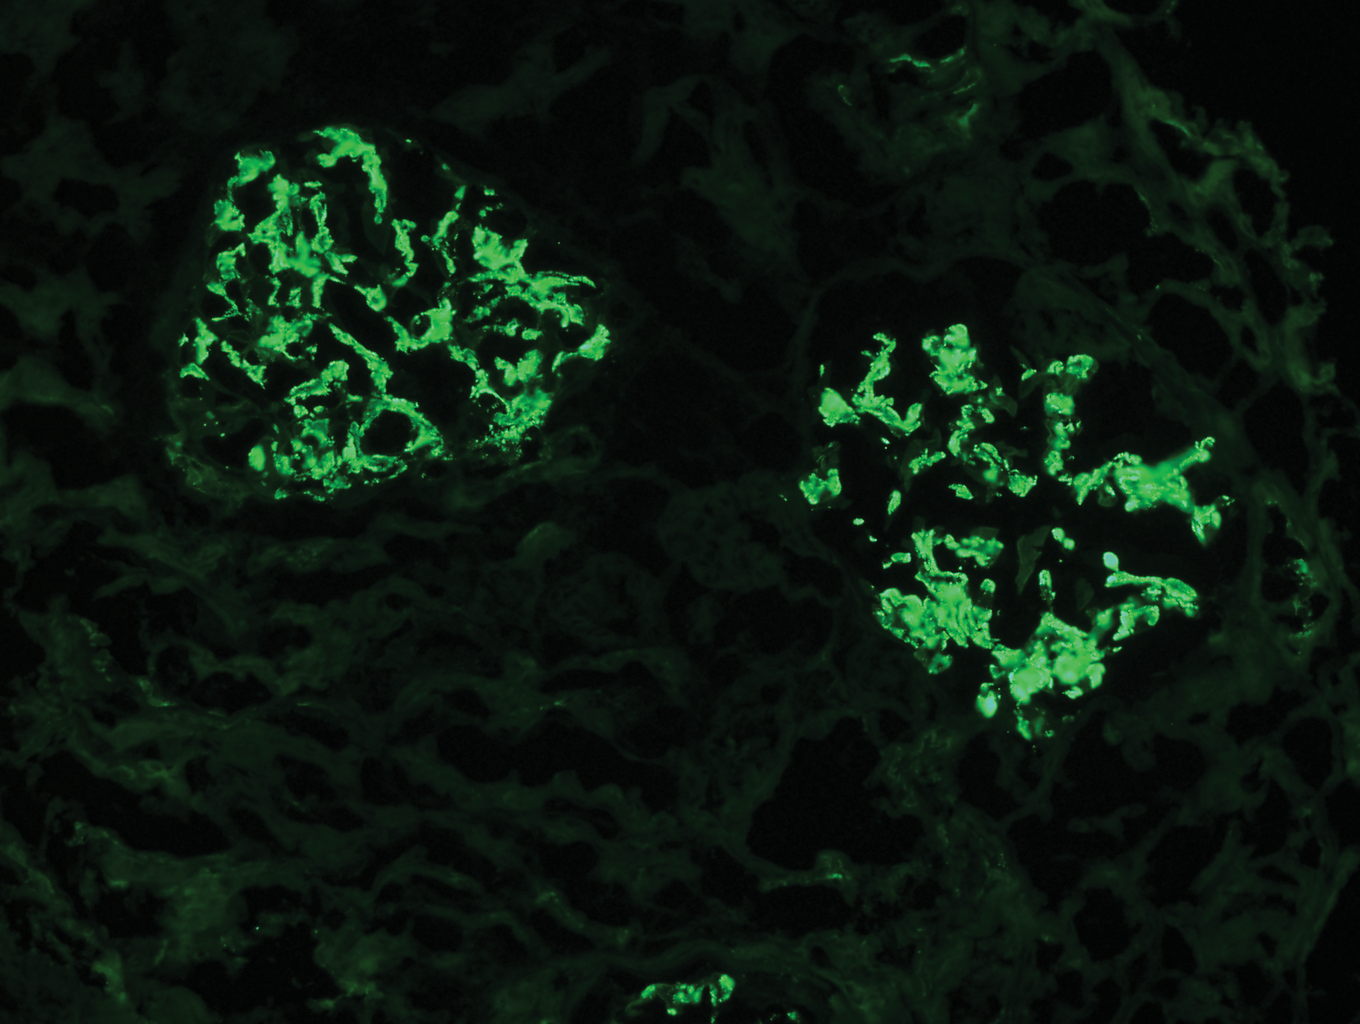

Question 4: The following is the FITC for IgG stained kidney specimen. What is this suggestive of?

- A. SLE (Correct Answer)

Explanation: ***SLE*** - **Lupus nephritis** (a kidney manifestation of SLE) often shows a "full house" immunofluorescence pattern, including **IgG deposition**, along with IgA, IgM, C3, and C1q [1]. - The presence of **IgG staining** in a kidney biopsy is a common finding in various forms of lupus nephritis, such as diffuse proliferative glomerulonephritis [1,5]. *Buerger's disease* - This is a **vasculitis** primarily affecting small and medium-sized arteries and veins, typically in the limbs. - It does **not primarily involve the kidneys** with IgG deposition and is not diagnosed via kidney biopsy immunofluorescence. *Goodpasture syndrome* - Characterized by **linear deposition of IgG** along the glomerular basement membrane (GBM) on immunofluorescence. - While it involves IgG, the question implies a more general IgG staining, and Goodpasture's has a very specific **linear pattern**, which is distinct from the granular or mesangial patterns often seen in SLE [2]. *Membranous glomerulonephritis* - This condition is characterized by **granular subepithelial deposits of IgG and C3** along the glomerular basement membrane [1]. - While it involves IgG, the question's image (if implied) would likely show a more diffuse, granular pattern, and SLE can also present with IgG, but often with other immune complex components, making SLE a broader and often more complex picture [2]. **References:** [1] Cross SS. Underwood's Pathology: A Clinical Approach. 6th ed. Common Clinical Problems From Diseases Of The Urinary And Male Genital Tracts, pp. 532-533. [2] Kumar V, Abbas AK, et al.. Robbins and Cotran Pathologic Basis of Disease. 9th ed. The Kidney, p. 911. [3] Kumar V, Abbas AK, et al.. Robbins and Cotran Pathologic Basis of Disease. 9th ed. Diseases of the Immune System, pp. 230-232.